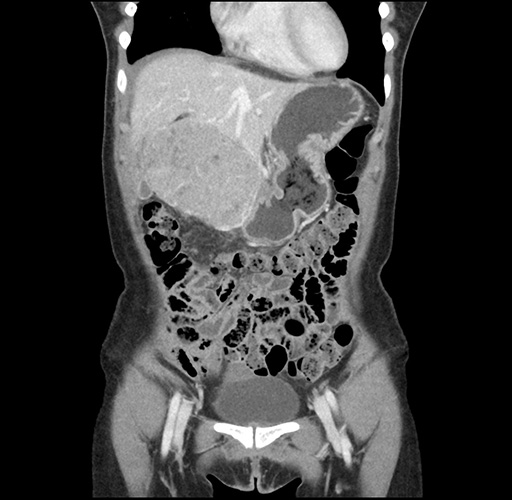

Imaging Analysis

Look through the patient's CT scan to identify any areas of concern for the necessary procedure.

Based on your CT findings, which issue(s) would give reason for "planned slowing down moment(s)" in this case?

Considering a standard left lateral sectionectomy procedure, what step(s) of the operation would you do differently in this case ?